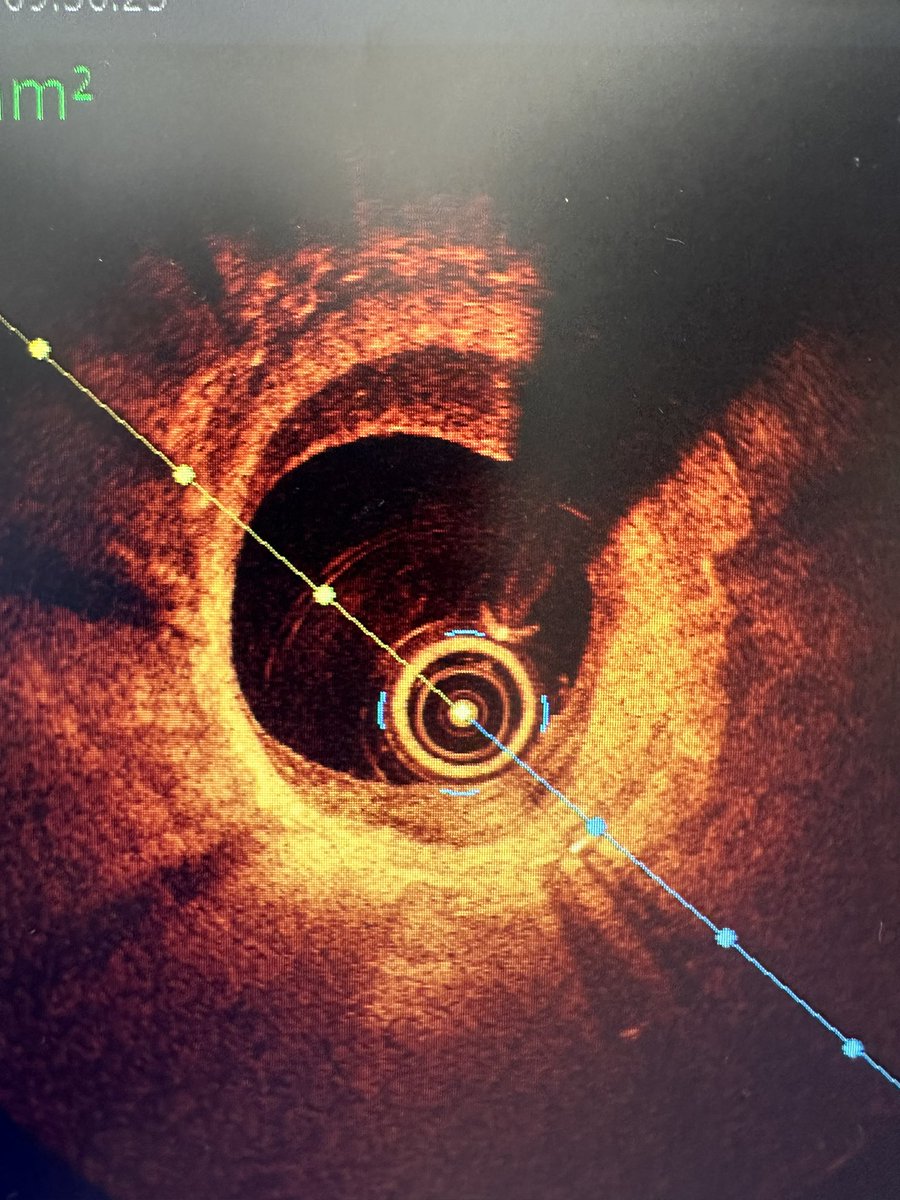

@ShaziaTHussain1 @DrPeterOKane @twj1974 @ziadalinyc @ALadwiniec @JonathanDWood1 @AbbottCardio @ShrillaB @mmamas1973 @ammozid Thanks for sharing these beautiful images. This is NIH with sessile thrombus which is now in the organising stages. I would have also used IVUS in this specific case to look at Adventitia and guide DCB treatment. Consider prolong DAPT and bring back at 9 months for repeat study.

@GopalKkoduru @DrPeterOKane @twj1974 @ziadalinyc @ALadwiniec @JonathanDWood1 @AbbottCardio @ShrillaB @mmamas1973 @ammozid I put in a DES in this case as significant atheroma either side of the stent.